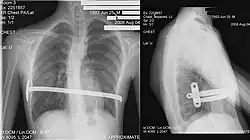

Röntgenbild eines männlichen 15-Jährigen nach einer Nuss-OP

Bei der sogenannten „Nuss-OP“, die erstmals 1998 von Donald Nuss beschrieben wurde,[17][18] wird durch zwei kleine Schnitte an den Seiten unter den Achseln ein individuell ausgemessener und vorgebogener Metallbügel unter das Brustbein geschoben. Dieser drückt das eingesunkene Brustbein und die betroffenen Rippen nach außen. Der Bügel wird seitlich fixiert. In manchen Fällen werden auch zwei oder drei Bügel eingebracht. Das Ergebnis ist sofort sichtbar.

Meist bleibt der Bügel für zwei bis drei Jahre im Körper und wird dann operativ entfernt; bei älteren Patienten ist eine längere Zeit erforderlich. Seit 1999 wird die Methode auch in Deutschland durchgeführt. Aufgrund der kleinen Narben ziehen viele Patienten diese Methode der offenen Methode nach Mark Michael Ravitch vor.[19]